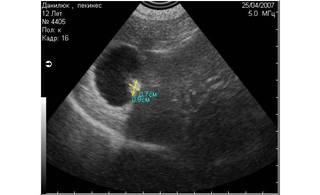

Например, при дифференциации конкрементов и новообразований в различных органах присутствие эхоакустической тени является ультразвуковым маркёром конкремента.

Рис. 8. На снимке представлен гиперэхогенный объект в полости мочевого пузыря, испускающий эхоакустическую тень. На основании этого артефакта, мы можем предположить, что этот объект является конкрементом. |

Рис. 9. На снимке представлен похожий по величине и эхогенности объект в полости мочевого пузыря, не испускающий эхоакустической тени. На основании этого признака, мы можем предположить, что изучаемый объект является новообразованием. |